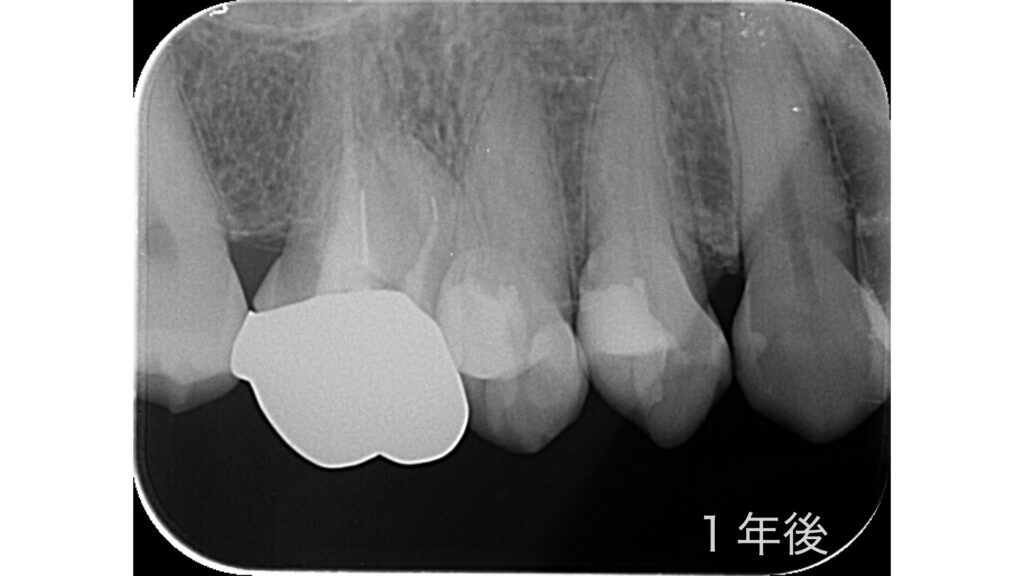

治療後の経過

1年余り経過した現在も、X線画像で炎症所見はなく、患者さんは日常生活を快適に過ごされています。今後も定期メインテナンスで経過を観察していきます。